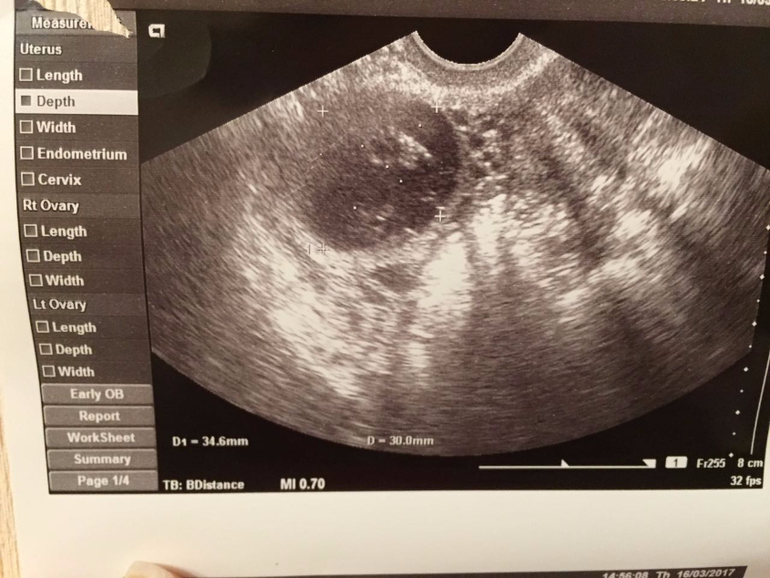

Задержка.Киста ЖТ.

Задержка М и нет БПосмотрите пожалуйста фотки,может кто то что то понимает.

Последний раз месячные были 30 января.Тесты пустые.

На узи сказали киста ЖТ,больше ничего не сказали.К врачу только на следующей неделе,а мне не дотерпеть!!Что мне делать?!?! Или чего наоборот не делать?!Помогите!